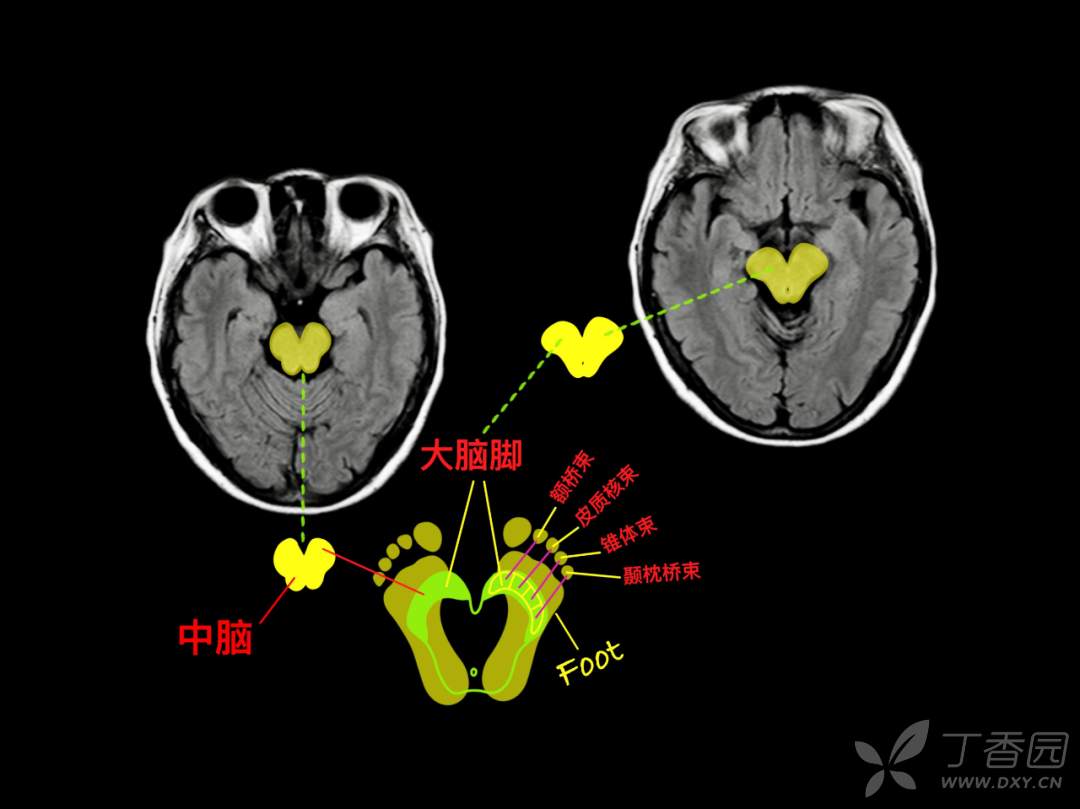

神经专业,要求「定位和定性」,先定位,后定性。与 CT 相比,颅脑 MR 可以更多、更清晰的呈现脑组织的解剖结构,神经专业的医生如何在颅脑 MR 的断层成像上去定位?

要么,你有「超级大脑」可以一层层的去记忆,「太难了」!那你也许会喜欢基于 「keypoint」的阅片方法,比如「苹果」外形、「Ω 征」、「M 征」等。本篇精华版 essay 希望给大家带来不一样的 MR 阅片技巧。

神经内科存在很多“征”,有助于帮助大家记忆!